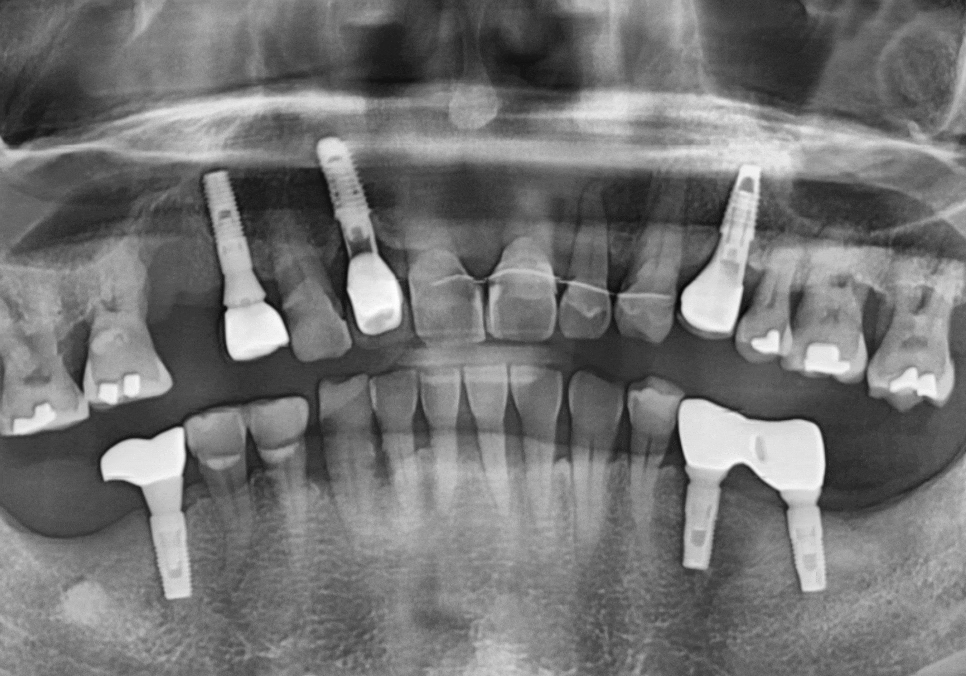

하지만, 방사선 사진과 입안을 살펴보니,

오른쪽 작은 어금니(#15) : 발치로 인해 치아 상실된 상태, 뼈가 다량 녹은 상태

앞니 3개 (#11,21,22) : 복합 치주염으로 뼈가 녹아 잇몸 상태가 좋지 않고 흔들림이 심함

250106 기존 뼈보다 녹은 뼈 상태

만약, 보장을 위해 1년 더 기다리게 된다면

앞니 쪽은 더 흔들리고

잇몸이 더 내려갈 가능성이 컸습니다.